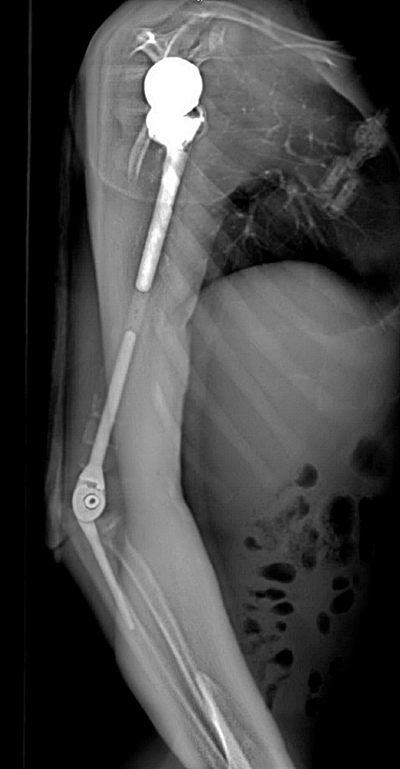

| Ảnh chụp X-quang tay phải của bệnh nhân sau khi phẫu thuật thay xương toàn bộ cánh tay |

Nhóm phẫu thuật đã lên kế hoạch sử dụng các công nghệ trong tái tạo xương hiện đại nhất hiện nay bao gồm tái tạo lại cấu trúc khớp vai, cấu trúc khớp khuỷu bằng vật liệu hợp kim titan. Đặc biệt, đội ngũ bác sĩ của trung tâm đã có một quyết định định táo bạo: không sử dụng hoàn toàn vật liệu kim loại mà chế tạo phần thân xương cánh tay sử dụng công nghệ in 3D vật liệu polyme sinh học (PEEK). Vật liệu này do phòng nghiên cứu ứng dụng công nghệ in 3D của Đại học VinUni sản xuất, giúp kết nối phần khớp vai và khớp khuỷu với nhau, đồng thời phục hồi lại điểm bám của các gân cơ quanh cánh tay. Đây được coi là một quyết định đầy tính sáng tạo dựa trên những nghiên cứu và thử nghiệm chuyên sâu từ nhiều ca bệnh đã thành công của ê-kíp phẫu thuật.

Theo các bác sĩ của trung tâm, công nghệ in 3D được coi là công nghệ duy nhất hiện nay mang lại khả năng cá thể hóa các chi tiết cấy ghép. Nhờ công nghệ này, cả 3 phần của xương cánh tay nhân tạo đều được “thiết kế riêng” theo đúng kích thước cánh tay thật của bệnh nhân, đồng thời có các điểm cố định giúp khôi phục lại hệ thống gân cơ bám xương. Trước khi sản xuất, tất cả những thiết kế này đều được thử nghiệm mô phỏng khả năng vận động, chịu lực trên máy tính. Nhờ vậy, xương nhân tạo sau ghép sẽ tương thích tối đa, “hoàn toàn vừa vặn” với cơ thể người bệnh và thời gian phục hồi chức năng vận động của cánh tay sẽ được rút ngắn đáng kể.